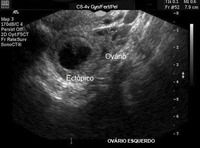

Gravidez ectópica: imagem de ultrassonografia de gravidez ectópica

Do acervo pessoal de Dra. Melissa Fries, Washington Hospital Center; usado com permissão